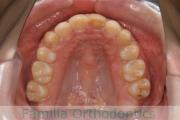

No.21V-298

- 上顎前突

- 叢生

- 25歳

- 女性

- 抜歯部位

- 上:

- 44

- 下:

- 55

- 主な使用装置:

- FEA

- 治療にかかった費用:

- 90万円

でこぼこと口元が出ている横顔が気になるとのことで来院されました。重度の叢生(ガタガタ)と側方へのズレがあるため、アンカースクリューを併用したマルチブラケット法にて治療を行いました。3年弱、35回程度の通院をしていただきました。叢生が強いため、部分的にガタガタが再発・後戻りするリスクが高いケースでした。